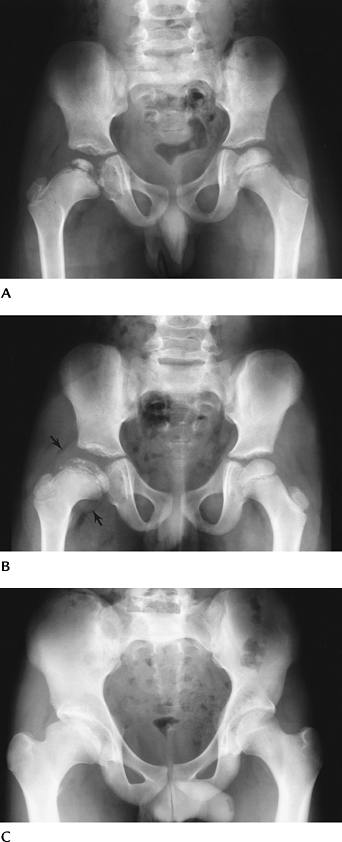

![]() |

FIGURE 4-51 AP (A) and oblique frog-leg views (B,C) of a slipped capital femoral epiphysis on the left. AP view (A) shows osteopenia and widening of the physis (arrows). Note the line along the lateral neck does not intersect the ossified epiphysis. The right hip (B) is normal. The displacement of the capital epiphysis on the metaphysis (lines) is obvious on the frog-leg oblique view (C).